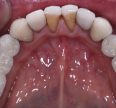

Composite Filling Replacements

Composite sometimes pits and sometimes fractures over time, leading to lack of hermetic sealing and risk of caries development.  In this case, the old composite exhibited marginal failure and physical […]